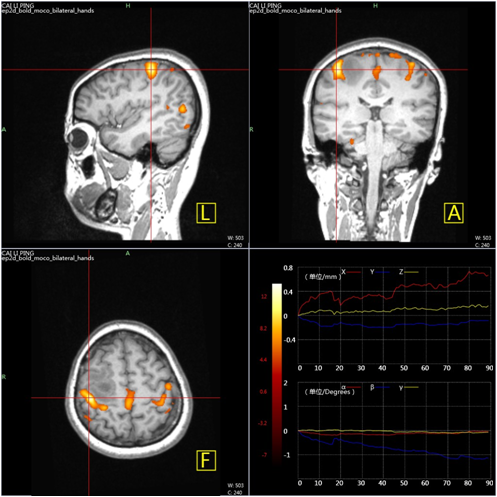

第二项新产品:磁共振影像处理软件,是一套对磁共振系统采集的功能磁共振图像进行处理的软件系统。该系统专为临床fMRI应用而设计,简化了任务态fMRI数据处理的流程,能够让医生摆脱对繁杂的科研型软件的依赖,仅需几次点击便能获取功能任务的激活脑区。同时,该软件产品附加了科研功能,集成了视听觉、运动和语言等刺激范式,并可将fMRI影像处理结果发送至导航系统或PACS系统,与多家导航设备实现完美兼容,从全链条上减轻了临床人员开展fMRI工作的负担。